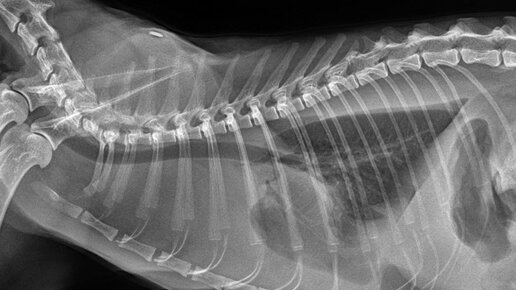

Подход к кошке со скоплением свободной жидкости в грудной полости

Сегодня на обсуждении достаточно часто встречающийся симптом – скопление свободной жидкости в плевральной полости у кошек и подход к таким пациентам. Причин возникновения патологии достаточно много: ХСН (хроническая сердечная недостаточность) в стадии декомпенсации, гипоальбуминемия, лёгочная тромбоэмболия, неопластический процесс, вирусные инфекции ( FIP и пр.), абсцесс лёгкого, травмы грудной клетки и т.д. Основные механизмы скопления жидкости – это высокое капиллярное давление, высокая степень проницаемости сосудистой стенки, низкое онкотическое давление...